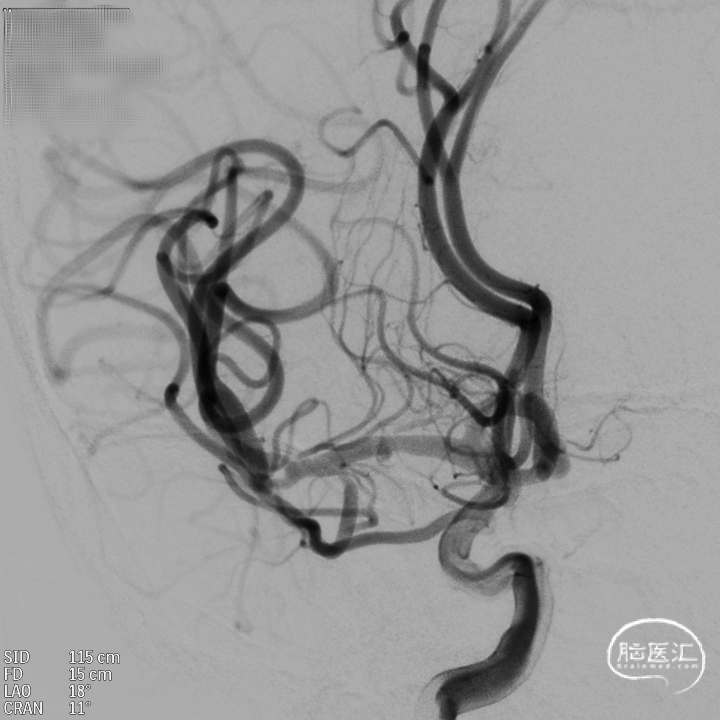

DSA:DSA提示右侧颈内动脉C6段可见多发动脉瘤。

其他血管造影未见明显异常。

术前诊断:右侧颈内动脉C6段多发动脉瘤。

治疗方案:血流导向装置植入术。

载瘤动脉远端血管直径:4.0mm

载瘤动脉近端血管直径:4.9mm、4.5mm(两个角度)

支架到位,远端打开(正侧位):4.75-20mm支架在大脑中动脉M1段打开,回撤至C6段远端锚定。支架释放过程中,轻柔推送支架系统,可见支架导管沿血管壁大弯侧走行,支架打开良好。

术后造影:支架覆盖两枚动脉瘤瘤颈,贴壁良好,瘤体内可见造影剂滞留。